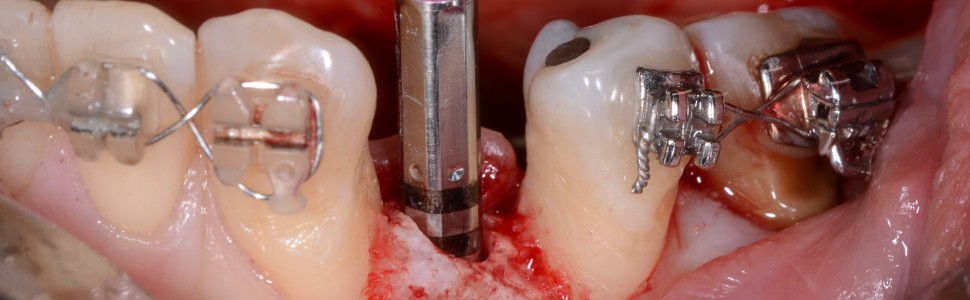

Artykuł przedstawia leczenie młodej pacjentki z zaawansowanym zapaleniem przyzębia. W procesie terapeutycznym konieczne było uwzględnienie procedur z zakresu periodontologii, ortodoncji i implantologii.

The article presents the treatment of a young patient with advanced periodontitis. In the therapeutic process, it was necessary to include periodontal, orthodontic and implant procedures.